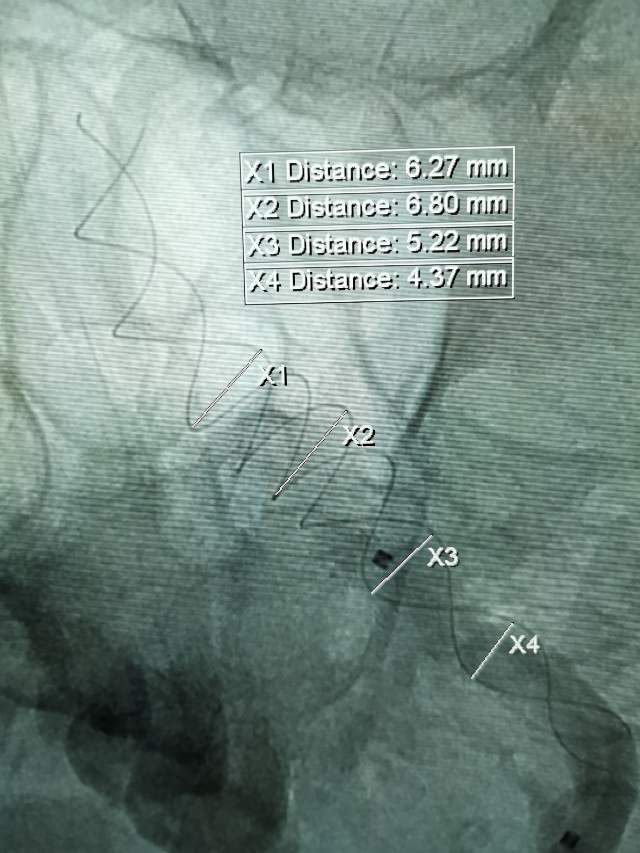

患者男性,34岁,年前自新疆坐车48小时来到我院,诊断:椎基底动脉冗长扩张症,出现脑干压迫症状、后组颅神经症状、部分中组颅神经症状、小脑症状、颅内压增高(220mmHg),症状进行性加重,最大径15mm,血管外面存在血栓造影只能窥见部分,短短两周,病变形态出现明显变化,局部出现明显瘤样凸起(图2-3),手术方案只能临时改变,植入血流导向装置,术后看病人语言、四肢活动均正常,围手术期仍然是一个艰巨的过程,充满了不确定因素,希望患者能安全度过围手术期,早日康复,重返工作岗位~~~